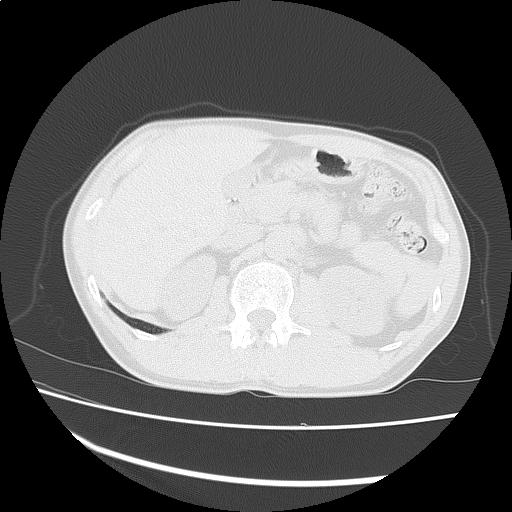

【読影指南】症例画像2

左第2肋骨神経鞘腫経過観察

年齢: 60歳

性別: 男性

検査部位: 胸腹部

検査種別: CT

CTスライス画像

CTスライス1